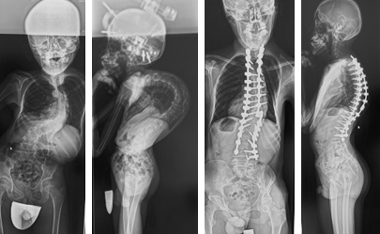

重度脊柱変形に対する矯正固定術

さまざまなお体の病気に伴い、せぼねが重度に変形を起こし息切れなどの症状が出る場合があります。

これらの患者様に対しては状況に応じて、せぼねを矯正固定する場合があります。小児科やリハビリテーション科と相談しながら手術時間や入院期間を検討していきます。